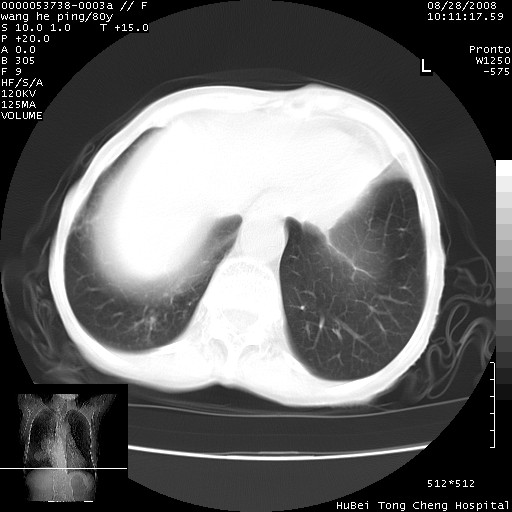

以下是引用黑白光影在2008-8-28 22:33:00的发言:[br]右肺中央型肺癌伴阻塞性肺炎,肺癌肺转移。

以下是引用lshx在2008-8-28 22:06:00的发言:[br]1.右肺中心型肺癌伴阻塞性肺炎,不除外双 肺早期转移。[br]2.心包积液。

以下是引用随光逐影在2008-8-29 7:40:00的发言:[br]1)右肺中心型肺癌伴阻塞性肺炎,肺内转移。2)心包积液(少量)。

以下是引用wqs571018在2008-8-28 21:56:00的发言:[br]右肺中心型肺癌伴阻塞性肺炎可能。

以下是引用liuyue在2008-8-28 22:46:00的发言:[br]1.右肺中心型肺癌伴阻塞性肺炎。[br]2.心包积液(少量)。